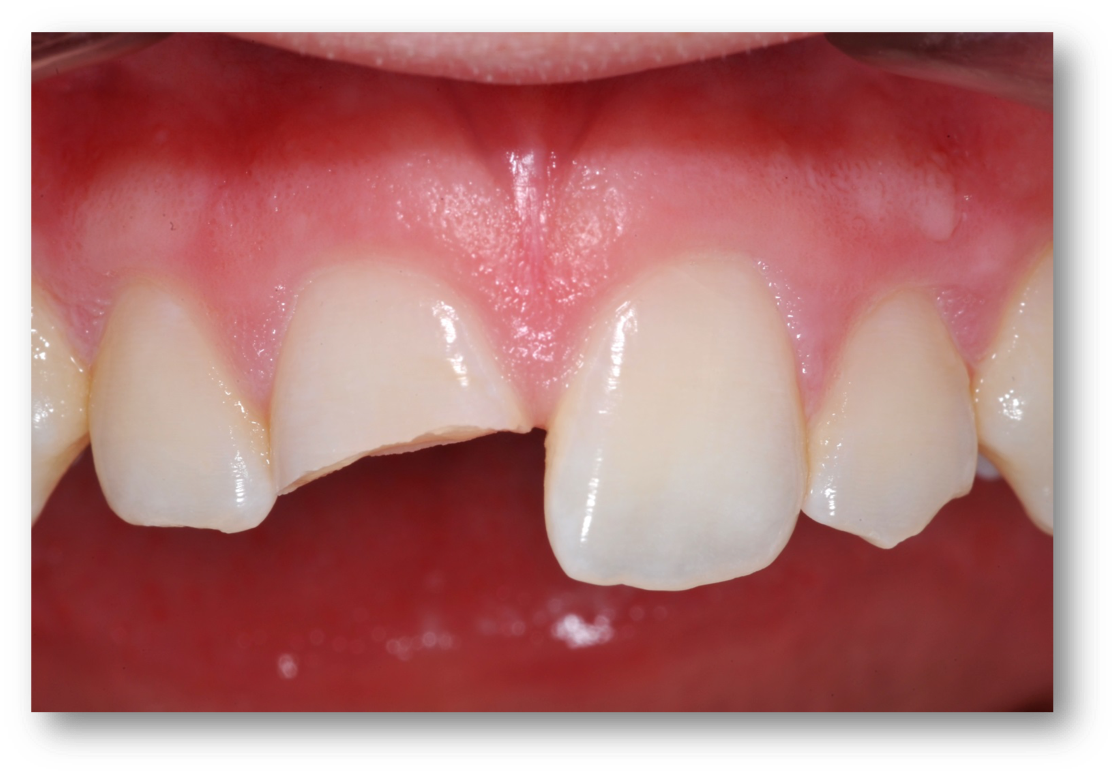

Example 3: Broken Tooth

Examples of broken-tooth situations can be seen in Figure 4 and Figure 5. Figure 4 was an emergency because the tooth broke, and there was also much decay. In determining when to stop drilling, the caries indicator is very important. Because in this case there was no preoperative pain, spontaneous pain, or periapical radiolucency, and bleeding was easily controlled, a direct pulp cap was performed.

In Figure 5, part of a tooth was knocked off by a Frisbee. The patient brought in the tooth part, which approximated back onto the tooth well. First, it was hollow-ground with a 330 bur to provide relief for liner. Then the piece that was broken off was etched, and the bonding agent was applied to it. The piece in the mouth was also etched, bonding agent was applied, and it was light-cured. Giomer flowable was placed over the bonded surface as it was held in place by the dentist. The assistant shined light at it and connected the piece that broke off to the tooth. To make the tooth stronger, a diamond or a bur is used to make an irregular bevel all over the facial surface and on the lingual. The strengthening comes mostly from the latter, and some esthetic improvement comes from the former. Bevels are kept all the way in enamel whenever possible. A total-etch technique was completed over the surface and then rinsed off. The bonding agent was then applied air-thin, and the flowable was squirted onto the tooth after each layer of composite, followed by a viscous hybrid applied over the flowable. The hybrid pushed the uncured flowable out to decrease the chances of voids that cause sensitivity and weaken the restoration. The tooth was then polished.

Fig 4. Emergency: broken tooth.

Figure 4

Fig 5. Tooth broken by a Frisbee.

Figure 5